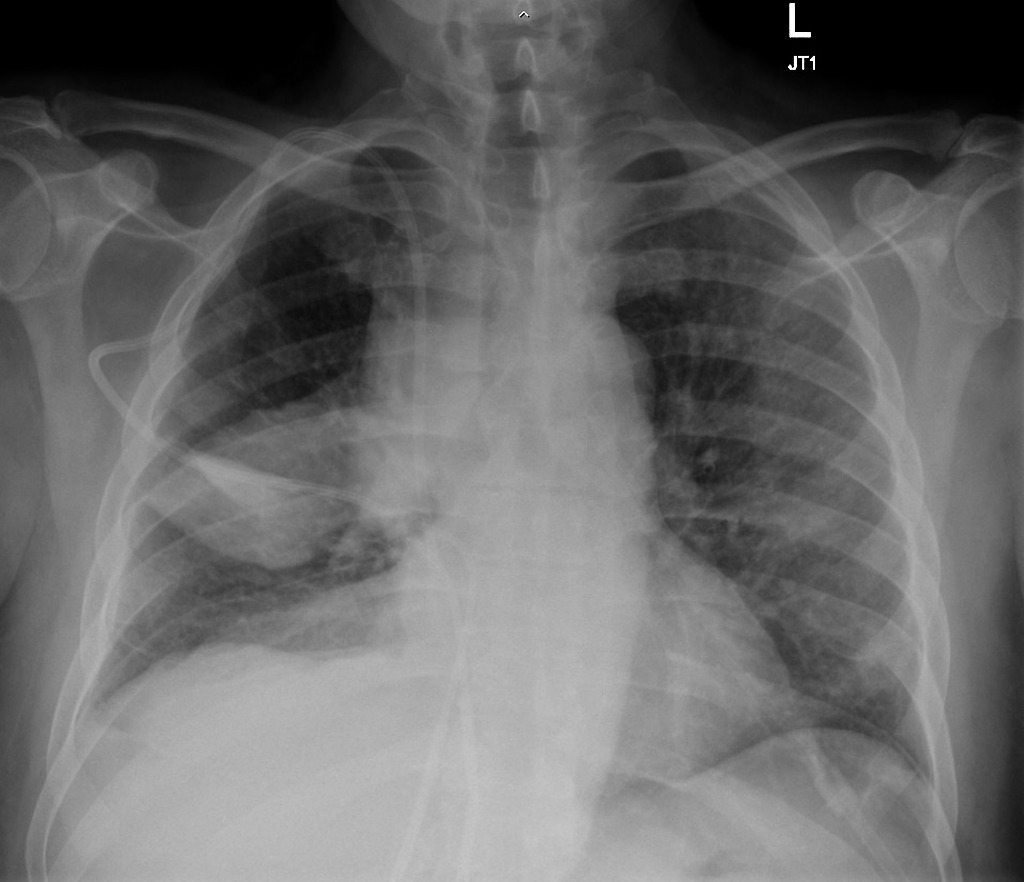

HOMEM DE 20 ANOS COM QUADRO DE INSUFICIENCIA RESPIRATÓRIA E HEMOPTISE. NEGA FEBRE

OPACIDADES DIFUSAMENTE DISTRIBUÍDAS, COM PADRÃO SUGESTIVO DE PREENCHIMENTO ALVEOLAR, PREDOMINANTE EM LOBO INFERIOR DIREITO

HEMORRAGIA ALVEOLAR